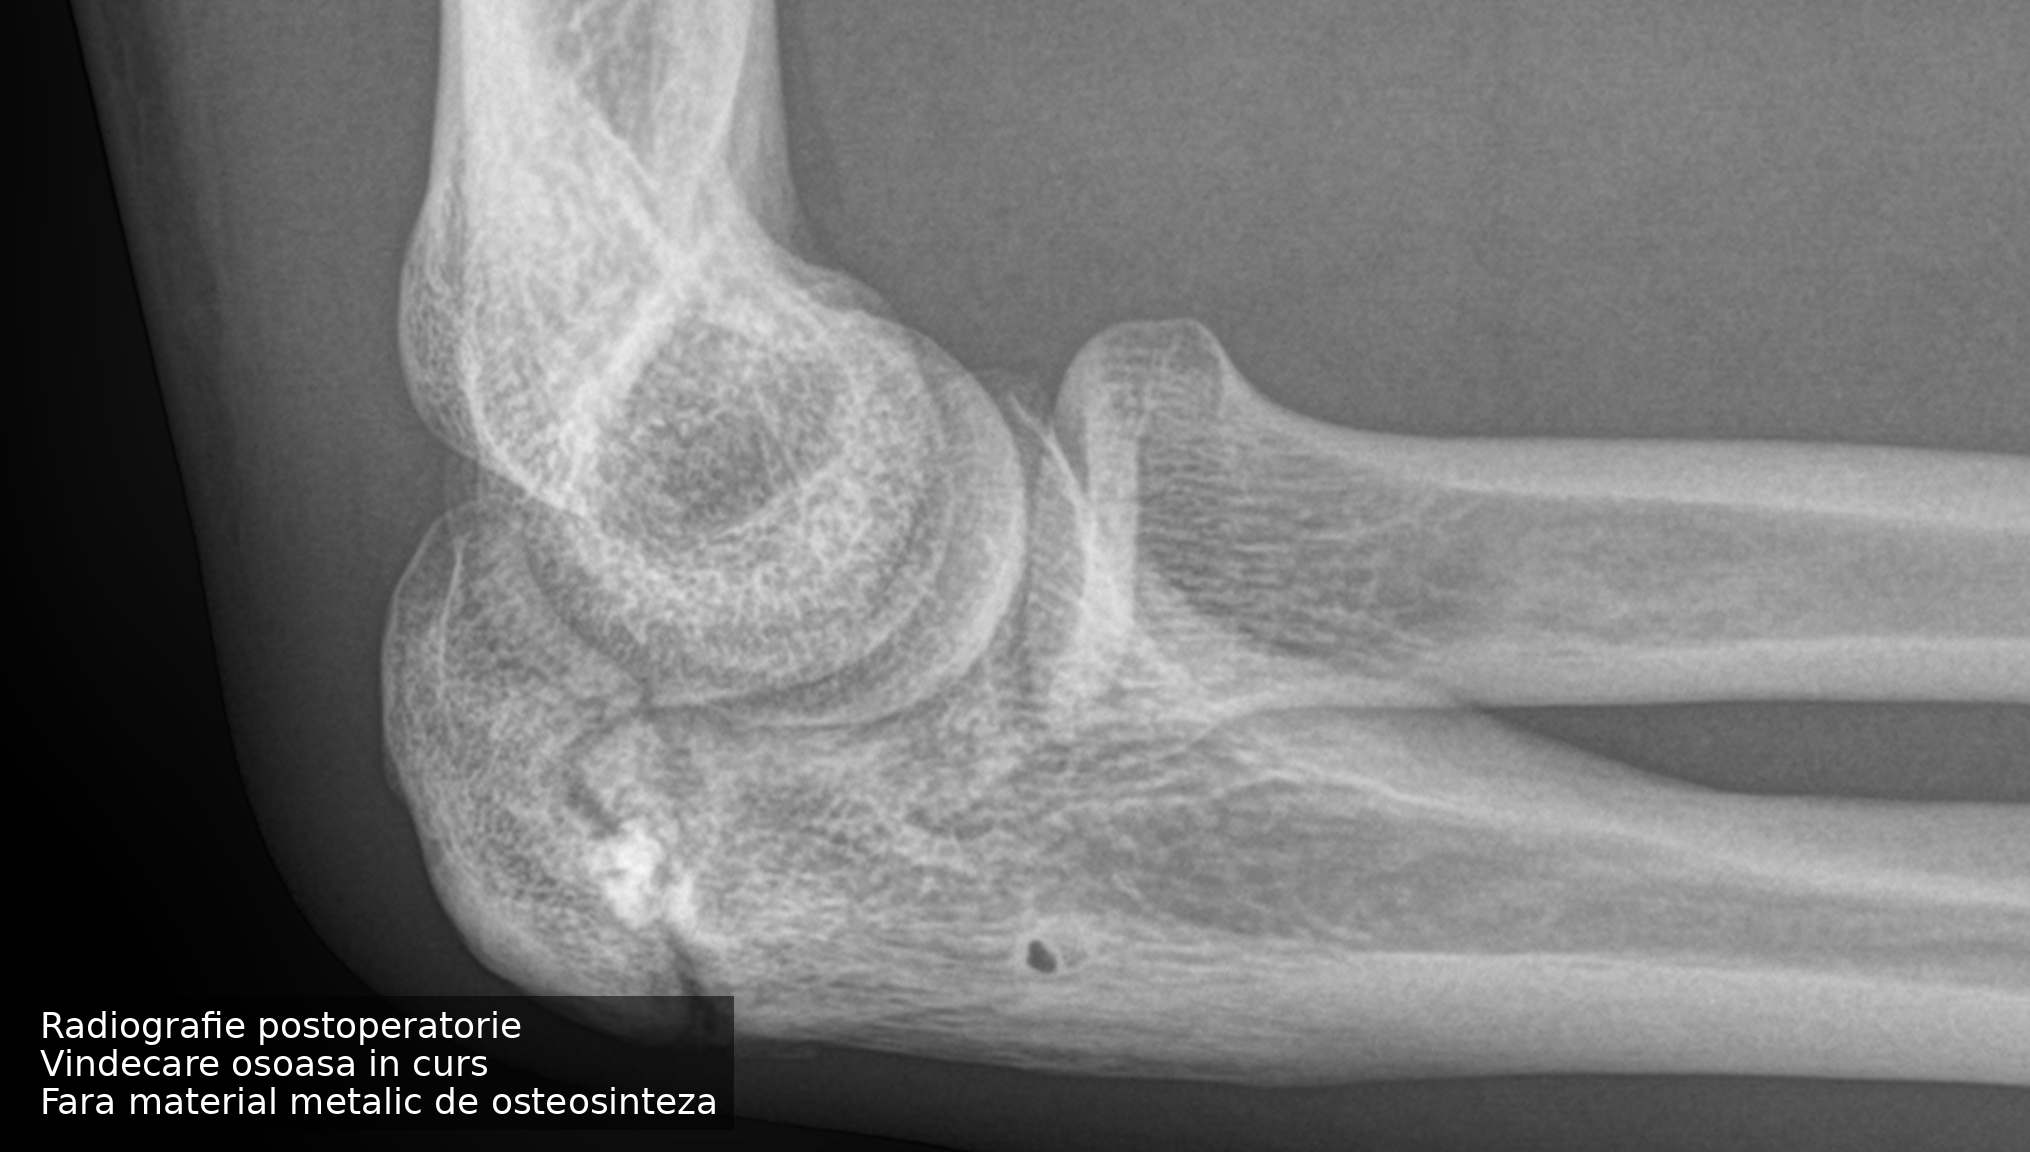

Pacientul a trecut printr-o suferință prelungită de aproape un an, perioadă în care durerile au progresat, iar forța la nivelul cotului a scăzut treptat. Sportivii sunt obișnuiți să funcționeze cu durere, iar în acest caz activitatea competițională a fost continuată în ciuda degradării progresive a funcției. La momentul primei evaluări, situația ajunsese într-un stadiu avansat. Traumatismele repetate specifice judo-ului au împiedicat maturizarea cartilajului de creștere în os, apofiza olecraniană rămânând separată de restul ulnei, cu apariția unui deficit osos vizibil radiologic.

Provocarea principală a fost reprezentată de deficitul osos asociat și de riscul unei fixări rigide clasice, care ar fi presupus aproape sigur o a doua intervenție pentru îndepărtarea materialului de osteosinteză. Pentru un atlet activ în competiții internaționale, acest lucru înseamnă nu doar timp pierdut, ci și un risc suplimentar pentru cot pe termen lung.

Am ales o soluție de fixare fără material metalic permanent, asociată cu augmentare osoasă, care să ofere stabilitate suficientă pentru vindecare, respectând în același timp biologia osului. Decizia a fost luată în urma unei discuții detaliate cu pacientul, în care obiectivul principal a fost revenirea la activitatea sportivă fără a compromite funcția cotului pe termen lung.

Evoluția postoperatorie a fost favorabilă, cu reluarea progresivă a activității și consolidare osoasă în curs. Revenirea în competiție a fost mai rapidă decât intervalele raportate frecvent pentru situații similare, fără a fi necesară o reintervenție. Vindecarea este încă în desfășurare, având în vedere deficitul osos inițial, însă obiectivele funcționale stabilite au fost atinse.